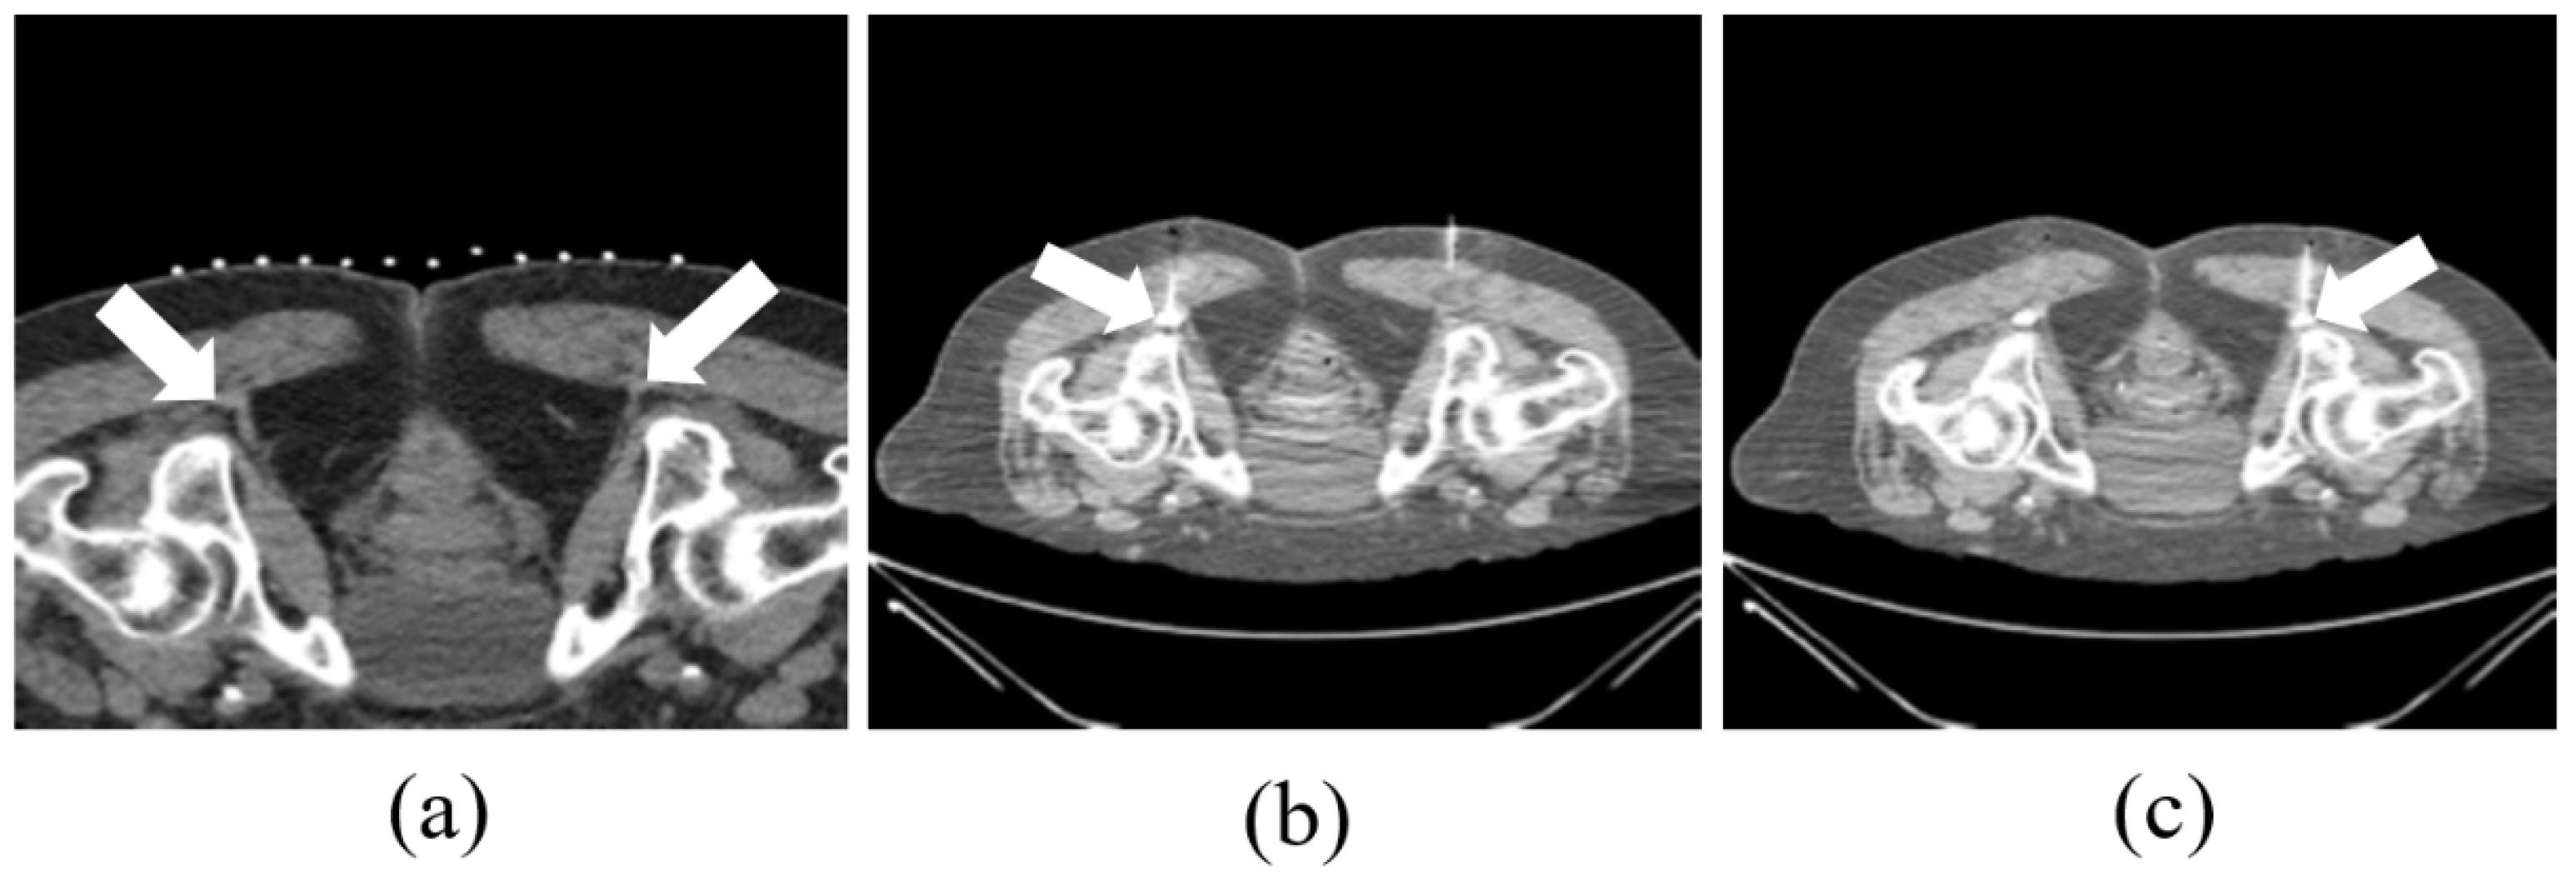

Procedure duration averaged 94 ± 46 minutes for pudendal cases and 49 ± 39 minutes for ilioinguinal/genitofemoral cases, including setup, sedation, and time-out protocols. Needle insertion-to-removal time ranged 5–10 minutes for pudendal and 5–20 minutes for ilioinguinal/genitofemoral cases. Technical success was achieved in all patients, defined as accurate needle placement confirmed with contrast injection and attainment of target ablation parameters. No immediate complications were observed. Demographic data, clinically relevant history, imaging studies, and details of medical and surgical therapy were abstracted from patients’ medical records. Ablation of respective pudendal nerves can be seen in Figure 2. Ablation of respective ilioinguinal and genitofemoral nerves can be seen in Figure 3 and Figure 4.

Figure 2. CT Acquisitions Portraying Pulsed Radiofrequency Ablation of the Pudendal Nerve. (a) Planning CT image demonstrates the isodense right pudendal nerve located posterior to an adjacent blood vessel; (b) Axial CT shows ablative changes following probe placement within Alcock’s canal targeting the left pudendal nerve; (c) Axial CT shows similar ablative changes with the probe introduced into Alcock’s canal targeting the right pudendal nerve.